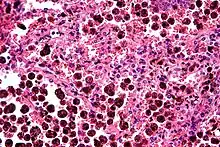

An alveolar macrophage, pulmonary macrophage, (or dust cell) is a type of macrophage, a professional phagocyte, found in the airways and at the level of the alveoli in the lungs, but separated from their walls.[1]

Activity of the alveolar macrophage is relatively high, because they are located at one of the major boundaries between the body and the outside world. They are responsible for removing particles such as dust or microorganisms from the respiratory surfaces.

Alveolar macrophages are frequently seen to contain granules of exogenous material such as particulate carbon that they have picked up from respiratory surfaces. Such black granules may be especially common in smoker's lungs or long-term city dwellers.